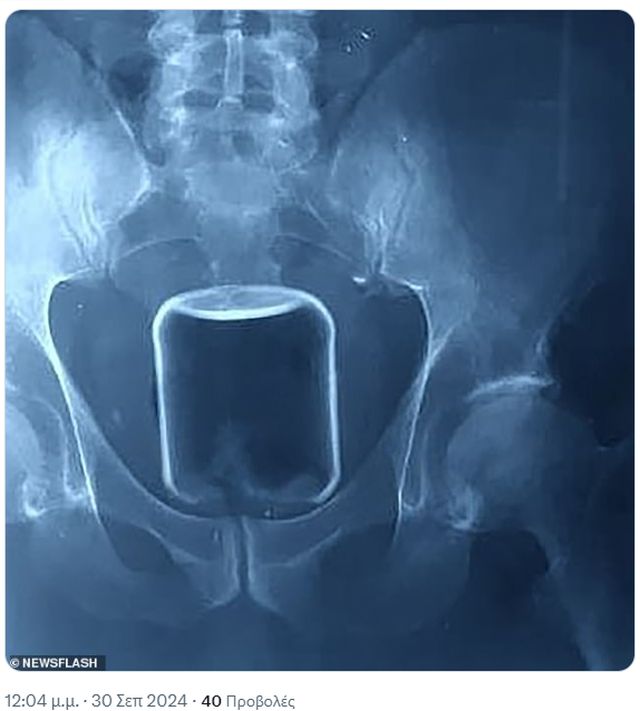

Οι γιατροί αφαίρεσαν με επιτυχία ένα μεγάλο γυάλινο βάζο από τον πρωκτό ενός άνδρα ύστερα από χειρουργική επέμβαση που ενείχε εξαιρετικά υψηλό κίνδυνο θανάτου.

Ο άνδρας, ο οποίος είχε μια ιδιαίτερη σεξουαλική πράξη, θα μπορούσε να είχε πεθάνει από αιμορραγία ή να είχε υποστεί θανατηφόρα βλάβη στα όργανά του, αν το γυάλινο βάζο έσπαγε μέσα του.

Οι γιατροί για καλή του τύχη κατάφεραν να αφαιρέσουν το αντικείμενο χωρίς να σπάσει.